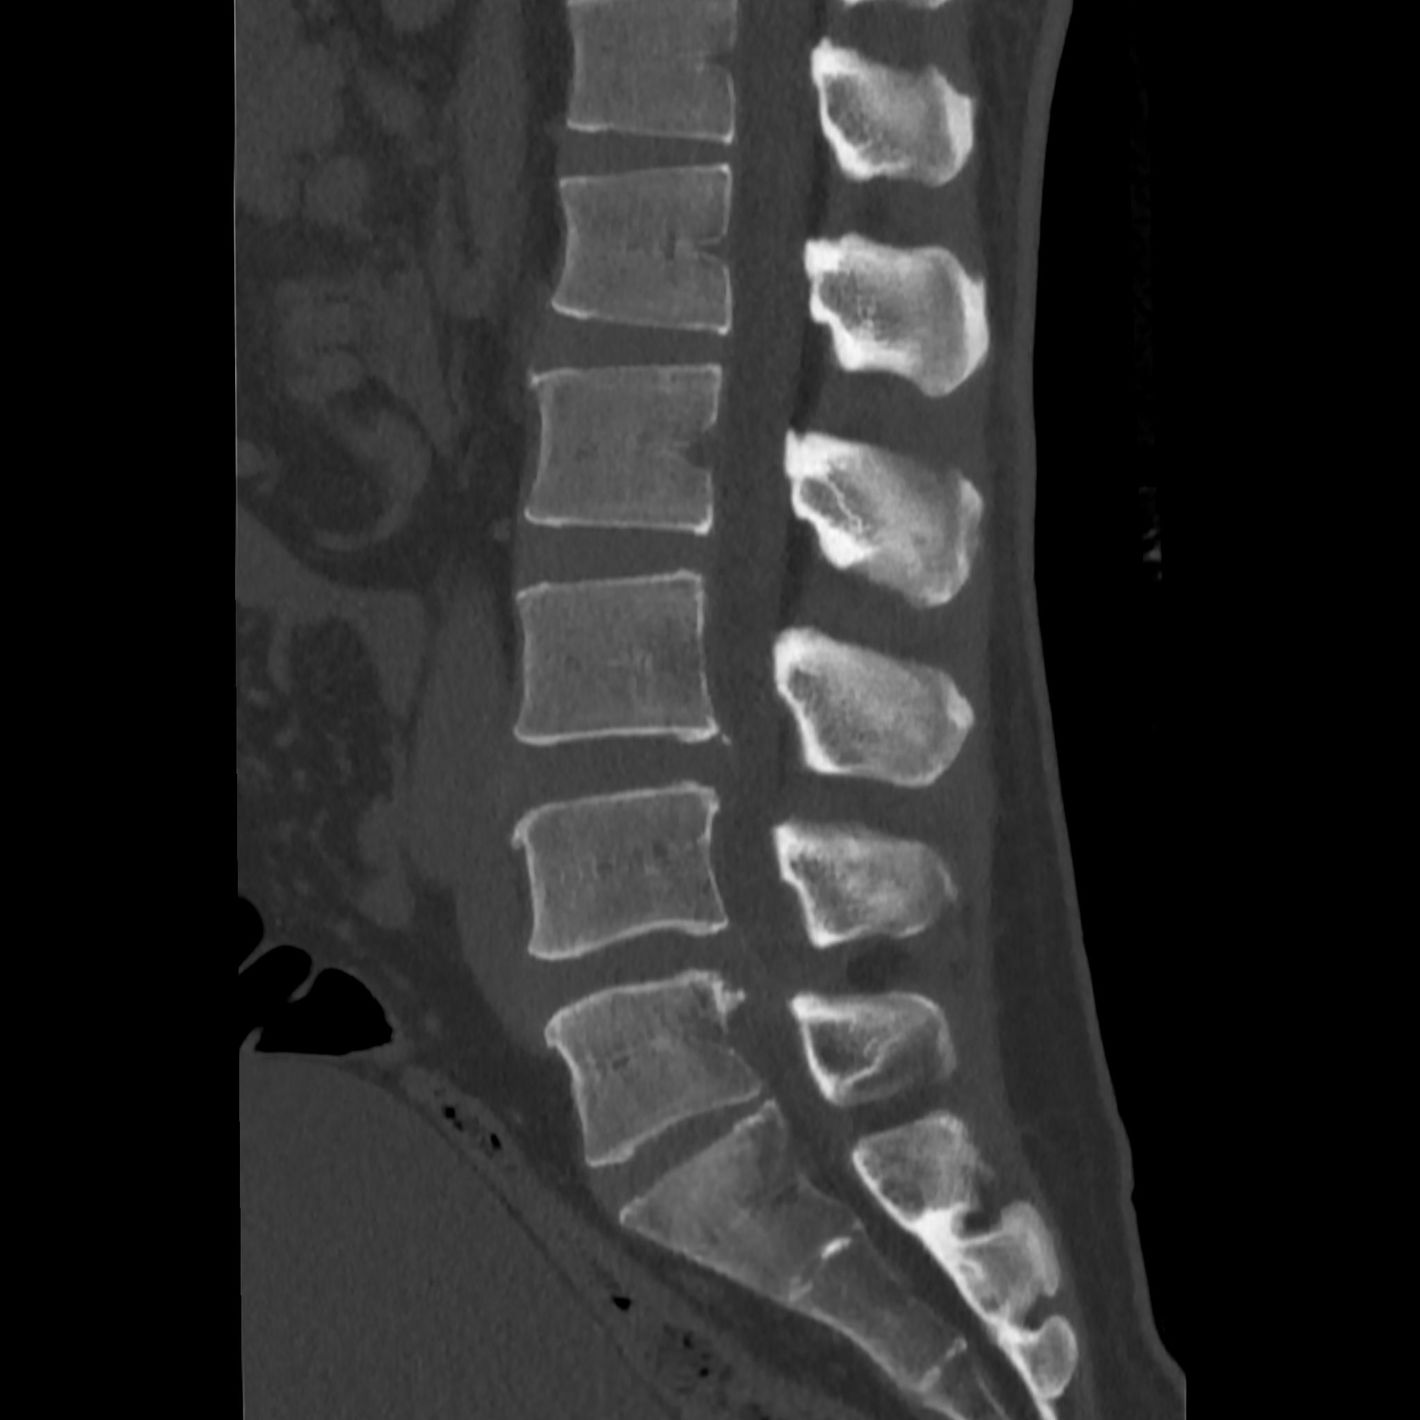

CTとMRIを融合した3D画像は、骨だけでなく椎間板や神経なども確認できるため手術をする際に作成される。(『

カニジル 18杯目

』より)